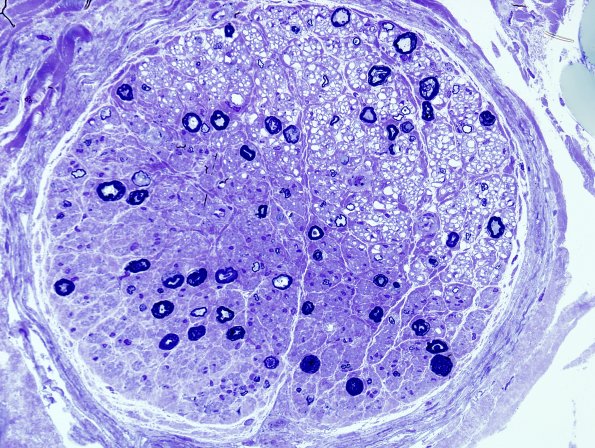

Washington University Experience | PERIPHERAL NEUROPATHY | 0 PNS ARTIFACTS | 9A2 Artifact, electrocautery Plastic 1.jpg

9A2,3 Higher magnification images of the effects of electrocautery. (Toluidine blue stained one micron thick plastic embedded sections)